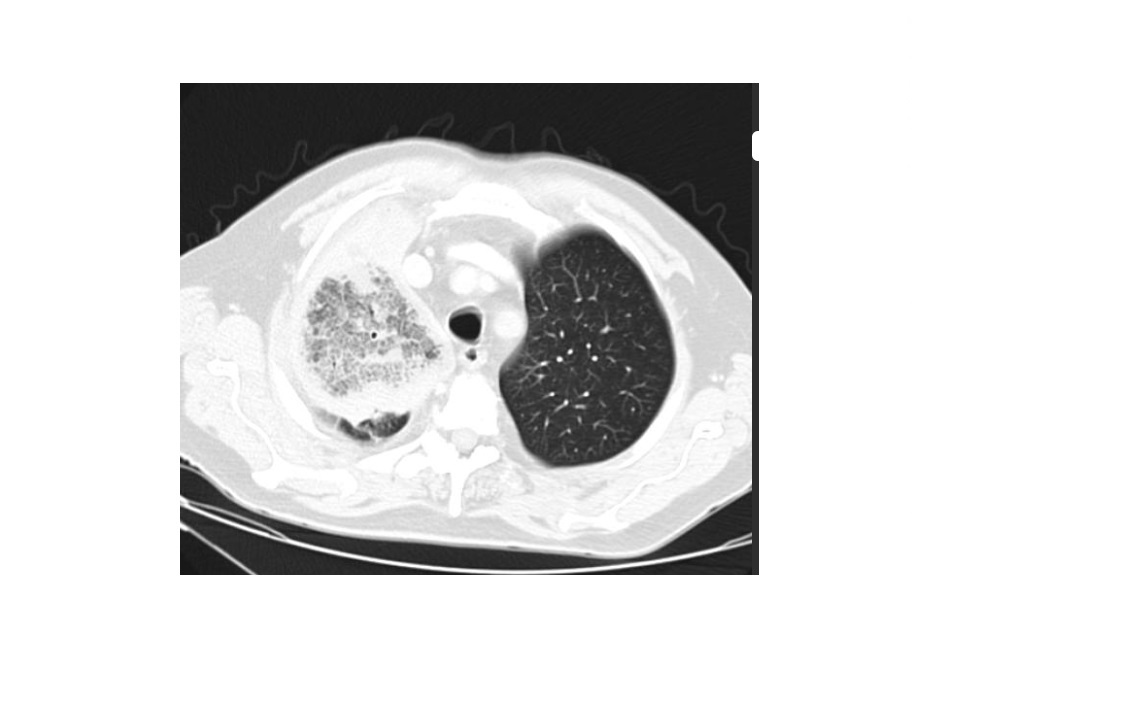

Angioinvasive aspergillosis

Halo sign

=Nodule/mass/consolidation surrounded by ground-glass opacity related to hemorrhage

Air crescent sign

=Crescent-shaped gas collection within nodule, mass, or consolidation

heralds improvement in the condition.